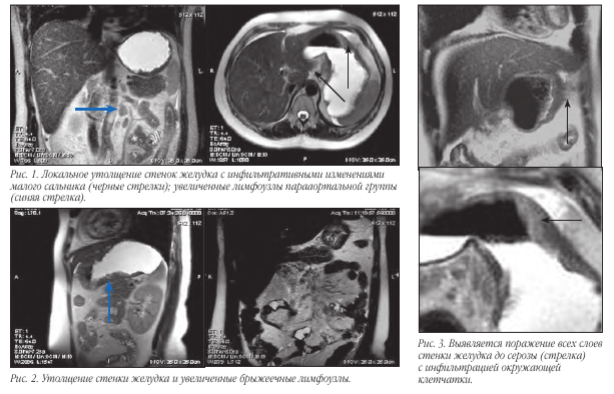

Методика исследования желудка включает в себя два этапа с предварительной подготовкой. Подготовка пациента к исследованию: за день до исследования исключить пищу богатую клетчаткой, принять «Фортранс», вечером выпить две таблетки «Но-шпы», очистительная клизма. Утром исследование проводится натощак с приемом двух таблеток «Но-шпы» за 20 минут до процедуры. Первый этап проводится на пустой желудок с использованием стандартных программ в коро- нальной, аксиальной и сагиттальной плоскостях взвешенных по Т2, Т1 с жироподавлением. На данном этапе оценивается состояние органов брюшной полости и забрюшинного пространства, диафрагмы, регионарных лимфоузлов, форма и расположение желудка, перигастральная клетчатка и абдоминальный отдел пищевода. Второй этап проводится при наполненном желудке. В качестве наполнителя используется обычная вода температуры 3б-37оС в количестве 3-4 стакана по 150 ml (450-600 ml).

Снова оценивается положение осей желудка, и срезы выставляются строго по осям, используя Т2ВИ. При нахождении подозрительного участка стенки желудка устанавливаются срезы толщиной до 3 мм параллельно и перпендикулярно патологической зоне, что позволяет определить протяженность поражения стенки, ее толщину, глубину поражения, наличие изъязвлений и нарушение целостности серозного слоя. В дополнение к Т2ВИ используются программы Т1 TRUFI и DWI.

В связи с тем, что визуализировать достоверно все слои стенки желудка чаще всего не представляется возможным, то критериями ее поражения являются степень утолщения и протяженности изменений. При поражении всех слоев и распространении процесса за пределы серозы основными МР-признаками следует считать нечеткость и размытость наружного контура стенки желудка, снижение сигнала от перигастральной жировой клетчатки. В современной лучевой диагностике МРТ применяется для определения стадии по N и M стадиям, используя TNM классификацию. Мы в своей работе используем классификацию Японской ассоциации по раку желудка. В основе классификации JGCA (1998) лежит анатомический принцип. В отличие от принципов JGCA, классификация UICC (Международного противоракового Союза 2002) рассматривает лишь количественное поражение регионарных лимфатических узлов вне зависимости от их локализации.